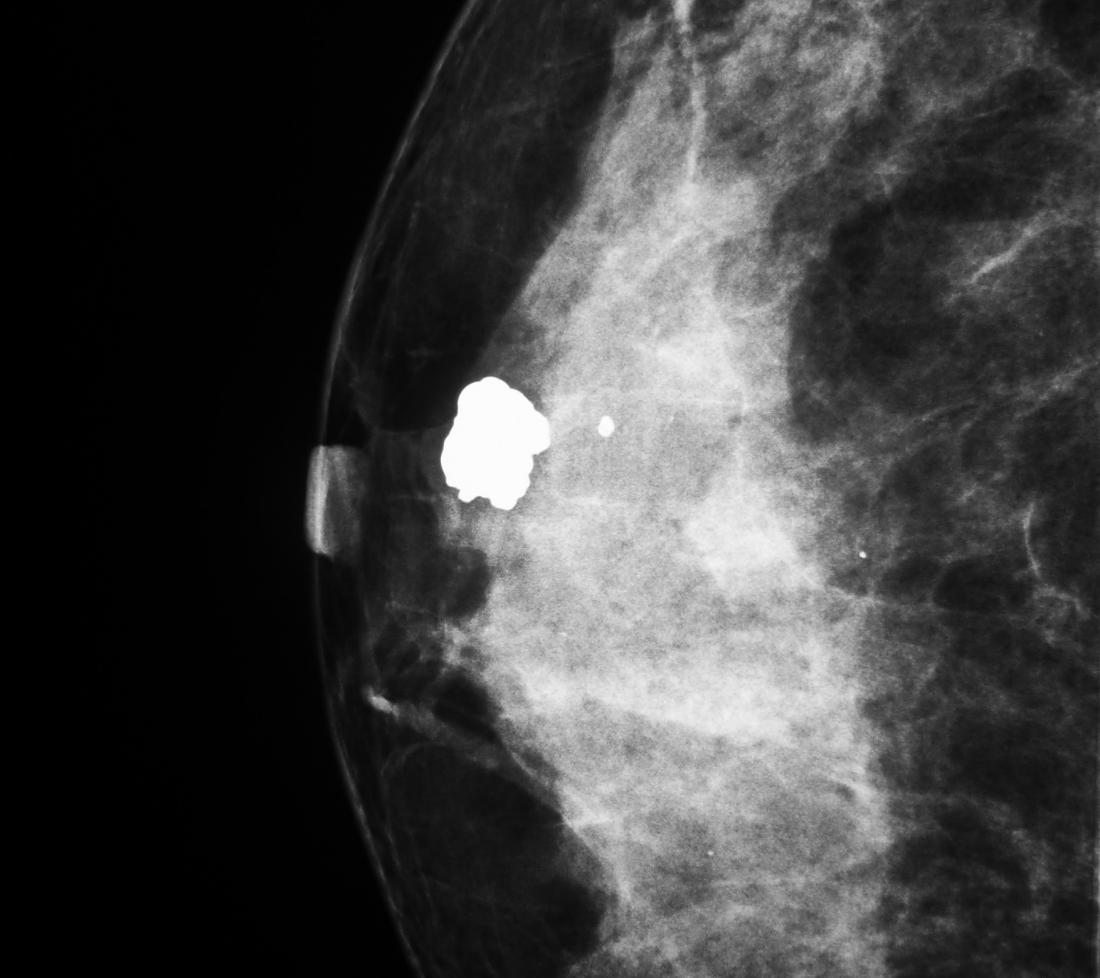

양성석회화는 저절로 없어지는 것이 대부분 이기도 하지만 악성석회화는 암세포 일부가 죽은 후 변성돼 생기기 때문에 유방암의 징후로 볼 수도 있습니다.

석회화는 모양을 보면 암 여부를 어느 정도 구별할 수 있습니다. 물론 모양만으로 암 여부를 명확히 구별할 수 없기 때문에 조직검사를 실시해야 합니다.

예전에는 외과적 수술로 조직검사를 했기 때문에 유방에 큰 흉터가 남게 되는 경우가 많았습니다만, 최근에는 입체정위 진공절제술을 통해 흉터를 거의 남기지 않고 석회화를 절제할 수 있습니다.